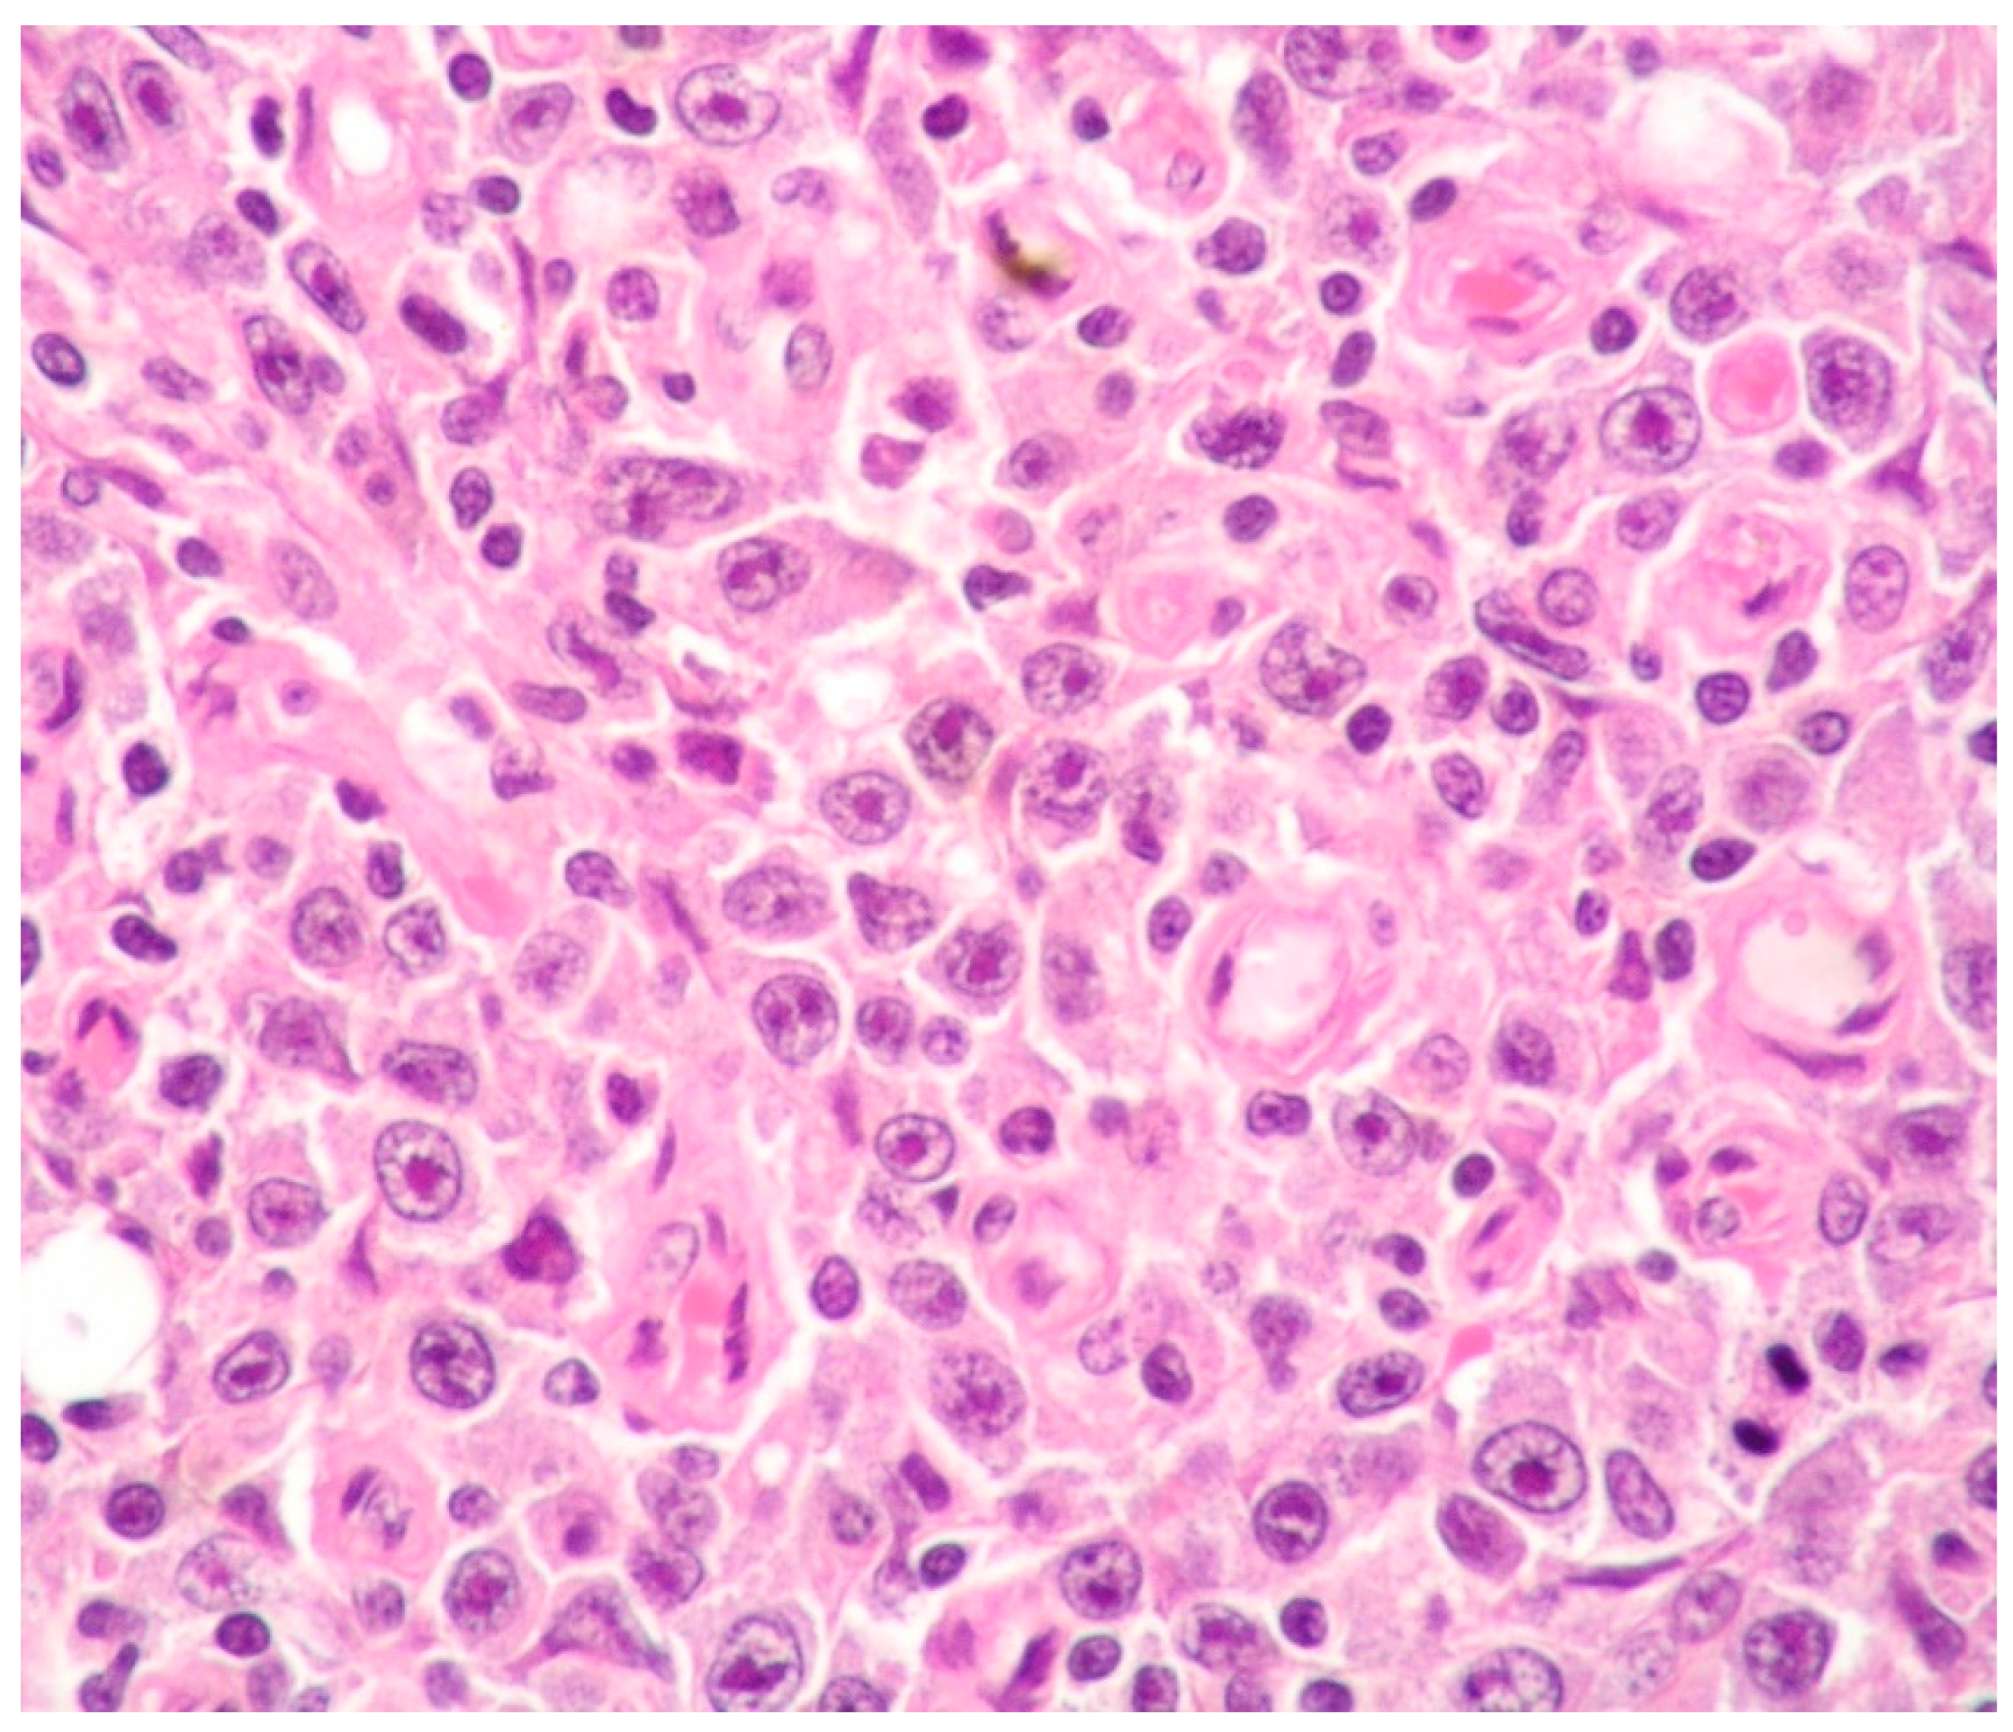

2.2. Morphology and Immunophenotype

| Histology | Large cells with IB and PB features | Diffuse proliferation of PBs/IBs | Sinusoidal and/or diffuse growth pattern of IBs and PBs | Sheets of PBs/IBs effacing organ architecture |